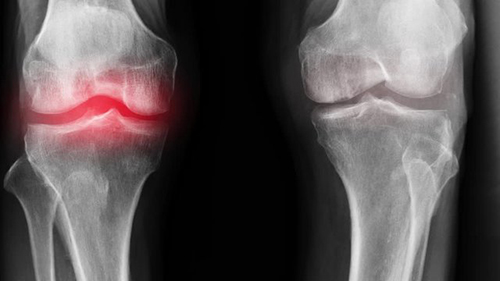

พวกนี้ไม่ช่วยเสริมสร้างข้อต่อหรือกระดูกอ่อนเลย พวกมันเพียงแค่ลดอาการชั่วคราว เช่น ปวด บวม อักเสบ ลองนึกดูว่าร่างกายจะเป็นอย่างไร เมื่อคนเรากินยา ทายาชา หรือฉีดยา ความเจ็บปวดก็จะหายไปชั่วคราว แต่เมื่อยาฤทธิ์หมด ความเจ็บปวดก็จะกลับมาอีก

อาการปวดเป็นสัญญาณสำคัญที่บ่งชี้ว่ามีความผิดปกติในข้อ การแค่ทำให้หายปวดจะทำให้สภาพของข้อต่อแย่ลง กระบวนการเสื่อมสภาพจะเร็วขึ้น 3-5 เท่า ส่งผลให้เกิดการเปลี่ยนแปลงที่ย้อนกลับไม่ได้ สูญเสียการเคลื่อนไหวและนำไปสู่การพิการในที่สุด

เมื่อเกลือเหล่านี้เกาะอยู่บนพื้นผิวของข้อต่อ คราบเกลือเหล่านี้เหมือนกระดาษทรายที่ทำลายเนื้อเยื่อรอบโดยรอบ กระดูก และกระดูกอ่อน เมื่อผลึกโตขึ้น เกลือจะเริ่มทำลายเนื้อเยื่อของกล้ามเนื้อ เอ็น หลอดเลือด และเส้นเลือดฝอย ทำให้เกิดการอักเสบ ติดเชื้อ บวม ก่อให้เกิดการอักเสบและปวดอย่างรุนแรง

ที่ญี่ปุ่น โรคข้อไม่ถือเป็นโรคอันตรายอีกต่อไป เว้นแต่เป็นกรณีบาดเจ็บรุนแรง เช่น กระดูกหักหรือร้าว อาการปวดและอักเสบที่ข้อเป็นเพียงสัญญาณว่าข้อเหล่านี้ "ปนเปื้อน" ด้วยเกลือ ถึงเวลาทำความสะอาดข้อแล้ว หลังจากทำ "คอร์สล้างเกลือ" เป็นเวลาหนึ่งเดือน ข้อก็กลับมาเป็นปกติ และคุณจะลืมปัญหาเหล่านี้ไปได้เลยในอีกสิบปีข้างหน้า